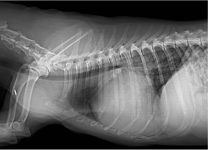

La radiografía de tórax y el TAC, ¿Cómo sacarles el mejor partido?